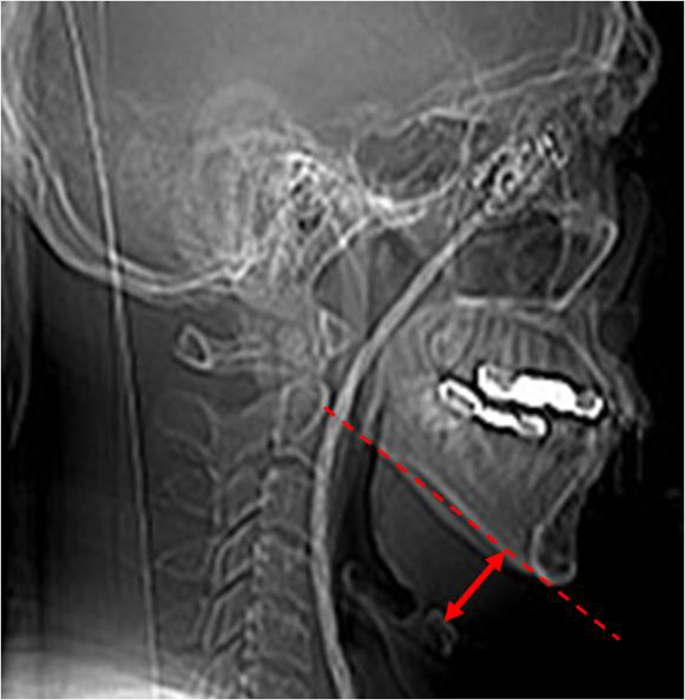

Measurement of the mandibular plane-hyoid distance

The distance from mandibular plane to hyoid bone was defined as ‘mandibular plane-hyoid distance (MPH)’ in lateral cephalometric analysis15,16. In this study, we utilized plain film of our CT series to take a measurement of the MPH (Fig. 4).